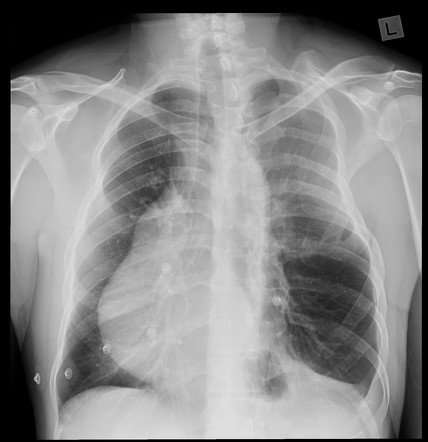

LearningRadiology - Poland, Syndrome

learningradiology.comsyndrome poland learningradiology here arrows left muscle same without click

Poland Syndrome | Image | Radiopaedia.org

radiopaedia.orgLiving With Poland Syndrome. How To Live With Poland Syndrome?

radiopaedia.orgLiving With Poland Syndrome. How To Live With Poland Syndrome?

Poland Syndrome – Radiology Cases

radiologycases.myPoland Syndrome - Stock Image - C021/1675 - Science Photo Library

radiologycases.myPoland Syndrome - Stock Image - C021/1675 - Science Photo Library

Poland Syndrome | Radiology Case | Radiopaedia.org

radiopaedia.orgPoland Syndrome Causes, Symptoms, Diagnosis, Treatment & Prognosis

radiopaedia.orgPoland Syndrome Causes, Symptoms, Diagnosis, Treatment & Prognosis

Poland Syndrome – Radiology Cases

radiologycases.myWhat Is Poland Syndrome And How To Treat It? – Healthy Food Near Me

radiologycases.myWhat Is Poland Syndrome And How To Treat It? – Healthy Food Near Me

healthy-food-near-me.comPoland Syndrome – Radiology Cases

healthy-food-near-me.comPoland Syndrome – Radiology Cases

Poland Syndrome | Radiology Reference Article | Radiopaedia.org

radiopaedia.orgsyndrome radiopaedia radiology

radiopaedia.orgsyndrome radiopaedia radiology

Poland Syndrome | Radiology Reference Article | Radiopaedia.org

radiopaedia.orgPoland Syndrome - Hand - Orthobullets